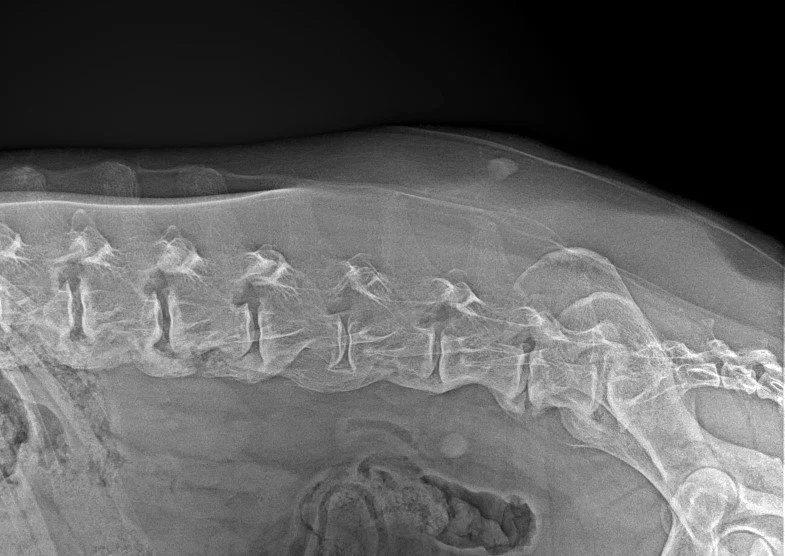

Spondylarthrosis

Diagnosis of severe Spondylarthrosis deformans.

Spondylarthrosis is a non-inflammatory degenerative condition that affects the vertebral bones of the spine. Osteophytes may form a complete bridge between adjacent vertebral bones, which is commonly referred to as “Spondylosis Deformans”.